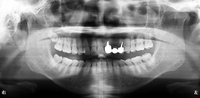

歯科治療の恐ろしさは、少しでも手を抜くと、積み重ねてきた治療効果が全て0=ゼロになってしまうことです。当院では一つ一つの治療過程にベストを尽くすべく、開業当初よりマイクロスコープ、セファロ分析や口腔内スキャンなど最新の機材を取り揃えて、幅広く、深い治療を追求してきました。

私はこれまでの歯科医師人生で、虫歯や歯周病、歯の根にある神経の処置である根管治療、入れ歯、インプラント、美容診療など、幅広く取り組んでまいりました。例えば虫歯治療では、痛みのある歯だけでなく、噛み合わせなどお口の中を総合的に考えたアドバイスや立案をし、歯を長持ちさせる処置を提供することを心がけています。